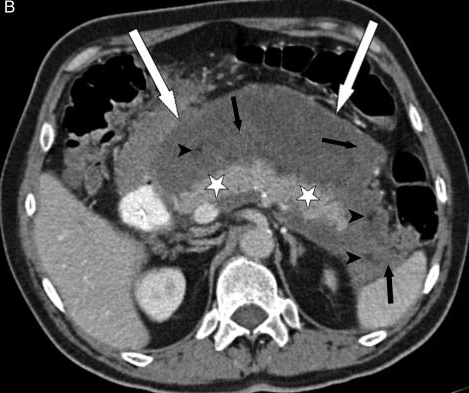

Nekrotizanpankreatit her zaman olmasa da genellikle ödematöz pankreatitten daha ağır klinik seyir gösterir. Nekrotizan-ödematöz ayrımını yaptıran yöntem kontrast maddeli bilgisayarlı tomografidir. Nekrotizan pankreatit üzerine enfeksiyon eklendiğinde ‘enfekte pankreas nekrozu’ olarak adlandırılır. Ağır bir klinik tablo olan bu durumda genel olarak nekroz cerrahi veya daha az sıklıkta da radyolojik olarak boşaltılamazsa ölüm oranı çok yüksektir. Nekrotizan ve enfekte nekrotizan pankreatitlerin tedavisi bu konuda deneyimli yoğum bakım uzmanlarının, radyologların ve cerrahların bulunduğu bir ortamda tedavi edilmelidir.

Enfekte pankreas nekrozu genellikle hastalığın başlangıcından 2-4 hafta sonra görülür. Hasta başlangıçtan beri hastanededir ve klinik olarak çeşitli problemler nedeniyle yatış süresi uzamıştır. Çoğu kez yoğun bakımda birden fazla organ yetmezliği gelişmiş durumdadır. Enfekte nekroz tanısı konulduktan sonra bu iltihaplı dokuların vücut dışına çıkartılması gerçekleşmezse hastayı iyileştirebilmek mümkün değildir. Bunu yapabilmek için de hastaların çok büyük çoğunluğunda bir veya daha fazla cerrahi girişim gerekir. Az sayıda hastada bunu girişimsel radyolojik yöntemlerle veya laparoskopik yapmak mümkün olabilir. Bu durumdaki hastalarda hastanede yatış süreci haftalar bazen de aylar sürebilir.

Akut pankreatitin seyri sırasında pankreas etrafında sıvı birikimi sık görülür. Bu toplantıların etrafında belirgin duvar yapısı yoksa ‘akut sıvı koleksiyonu’ olarak adlandırılır. Bunlar genellikle izlem sırasından herhangi bir işlem gerekmeden kaybolurlar. Eğer bu sıvı birikimlerinin etrafında belirgin duvar yapısı varsa ‘pseudokist’ olarak adlandırılırlar. Pseudokistlerin bir kısmı zaman içerisinde kendiliğinden iyileşebilir. Ancak boyutu 6 cm’den büyük olanlarda bu durum daha az görülür. Pseudokistler eğer herhangi bir probleme neden olmuyorlarsa uzun süre izlenebilirler. Komşu organlara bası belirtileri varsa, iltihaplanırlarsa veya içlerine kanama olursa girişim gerektirirler. Dışarıdan dren konulması, endoskopik işlemler veya cerrahi tedavi seçeneklerinin tercihi kistin konumuna, komplikasyonun ne olduğuna, hastanın genel durumuna göre değişkenlik gösterir. Hangi tedavinin uygun olduğuna hastayı takip eden cerrah-gastroenterolog-radyolog ortaklaşa karar verir.